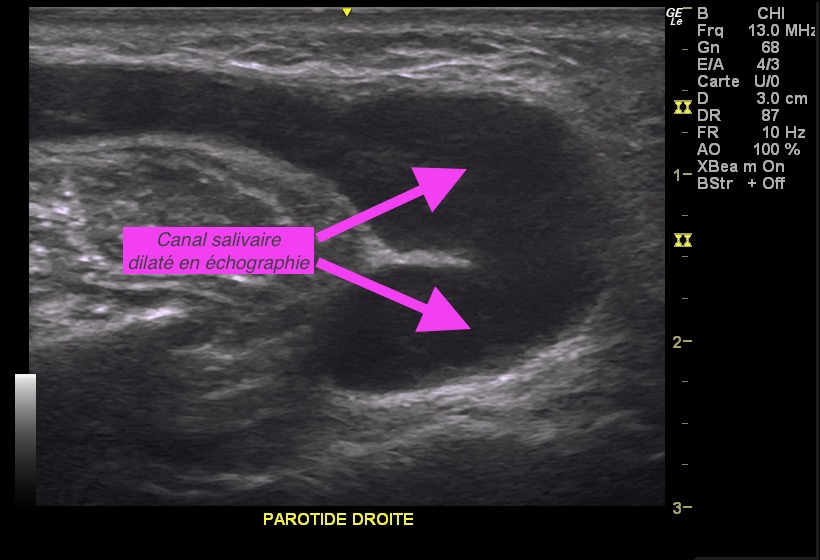

La prise en charge commence toujours par le bilan échographique spécialisé, un CBCT (Cone Beam Computerized Tomography) et si besoin et en dehors des périodes d’infections une sialographie ou un sialo-CBCT.

Des spasmes ou des sténoses des canaux évacuateurs peuvent créer les mêmes symptômes que les lithiases, avec des rétentions de salive et des blocages de la glande.

Il peut s’agir d’une sténose unique ou d’une vraie maladie sténosante avec des sténoses étagées entre des zones de dilatation dans tout le canal pour laquelle un traitement médicamenteux particulier doit être instauré. Dans certains cas une dilatation des sténoses sous endoscopie peut être envisagée.

En cas de dilatation majeure du canal en amont d’une sténose unique avec impossibilité de vidange de la salive, une chirurgie mini-invasive visant à récréer un orifice de sortie perméable est pratiqué.